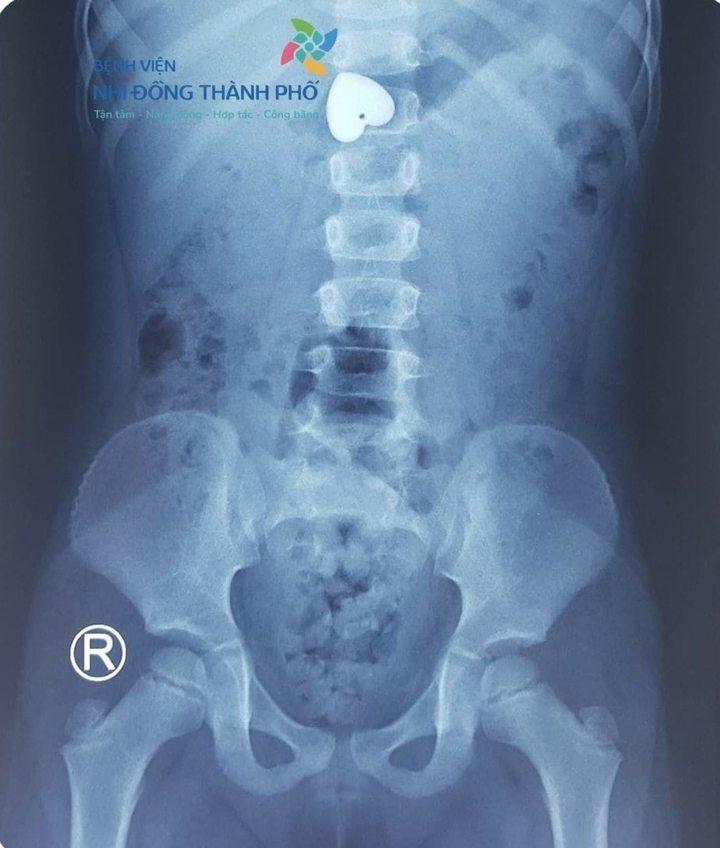

Qua quá trình chụp phim, bệnh viện cho biết mặt dây chuyền đã nằm trong bụng. Hiện, các bác sĩ đang kiểm tra lại những khâu hình ảnh quan trọng cuối cùng để xác định vị trí và tiến hành gắp nội soi. Nếu mặt dây chuyền đã xuống ruột và có nguy cơ tắc ruột thì buộc phải mổ để lấy dị vật ra.

Hiện mặt dây chuyền đã nằm ở bụng của bé. (Ảnh: bệnh viện cung cấp)